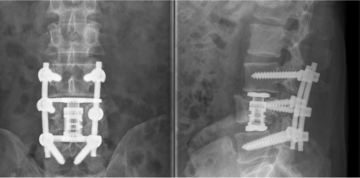

Der Wirbelkörperersatz kommt dann zum Einsatz, wenn instabile, oftmals aus mehreren Bruchstücken bestehende Wirbelkörperbrüche vorliegen und die Wirbelsäule nach vorne überkippen kann. Im Regelfall wird, wie bereits oben beschrieben, zunächst eine hintere Stabilisierung durchgeführt, um dann den zerstörten Wirbelkörper von der Seite her zu bergen. Hierbei wird ein Großteil des gebrochenen Wirbelkörpers entfernt und durch einen sog. „Cage“, einem künstlichen Wirbelkörper meist aus Titan oder hochwertigen Legierungen bestehend, ersetzt.

Ziel dieser Operation ist es, eine dauerhafte Festigkeit und knöcherne Verbindung zwischen dem ober- und unterhalb des gebrochenen Wirbels gelegenen Wirbeln zu erreichen, um somit eine belastungsstabile Wirbelsäule zu haben.

Hintere offene Stabilisierung durch ein Schrauben/Stab-System und Wirbelkörperersatz bei Bruch des 4. Lendenwirbelkörpers.